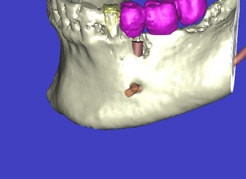

In komplexen Fällen, z. B. der Implantatversorgung eines kompletten Kiefers, oder bei schwierigen Knochensituationen bietet die 3-dimensionale Computerdiagnostik bzw. Planung und Durchführung erhebliche Vorteile und Sicherheit für den Patienten (siehe Bild 1 und 2).

Auf Basis einer computertomografischen (CT-) Kieferaufnahme ist eine dreidimensionale Darstellung der Knochen möglich. Der Zahnarzt kann dann am Computerbildschirm die Knochenqualität (z. B. Knochendichte) beurteilen und die optimale Position der Implantate im Vorfeld planen. Durch Verwendung spezieller Röntgenschablonen lässt sich auch die erwünschte Zahnstellung in die Planung einbeziehen. Die Simulation der OP erlaubt, das zu erwartende Ergebnis mit größtmöglicher Sicherheit vorherzusagen und dem Patienten am Bildschirm zu veranschaulichen.

(siehe Bild 3 und 4).

Mit diesen gewonnenen Informationen und Planungen stellt der Zahnarzt interaktiv spezielle Bohrschablonen her. Diese ermöglichen eine exakte Positionierung der Implantate, so wie vorher am Computer geplant.